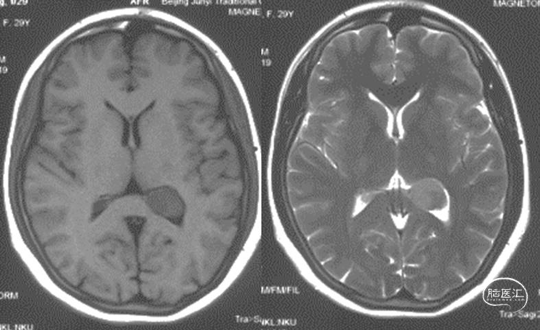

头颅MRI

头颅MRI增强

左侧侧脑室三角区脑膜瘤。